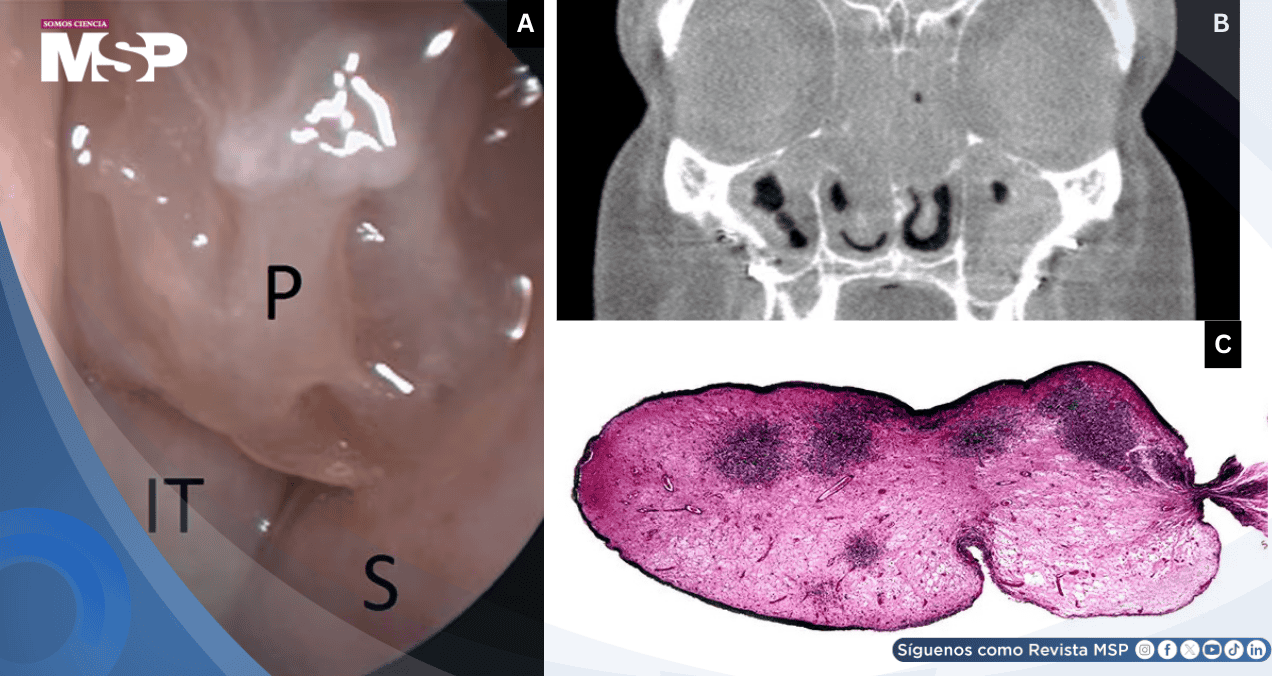

La tomografía computarizada de senos paranasales evidenció pansinusitis severa con opacificación completa o casi completa de todas las cavidades paranasales y nasales. Se identificó osteítis leve del hueso sinusal, sin compromiso de la lámina papirácea ni de la base del cráneo. Los hallazgos radiológicos fueron consistentes con un proceso inflamatorio crónico severo.

El estudio histopatológico de las lesiones polipoides confirmó un proceso inflamatorio eosinofílico sin evidencia de granulomas, lo cual descartó entidades como la granulomatosis eosinofílica con poliangiitis o la granulomatosis con poliangiitis.